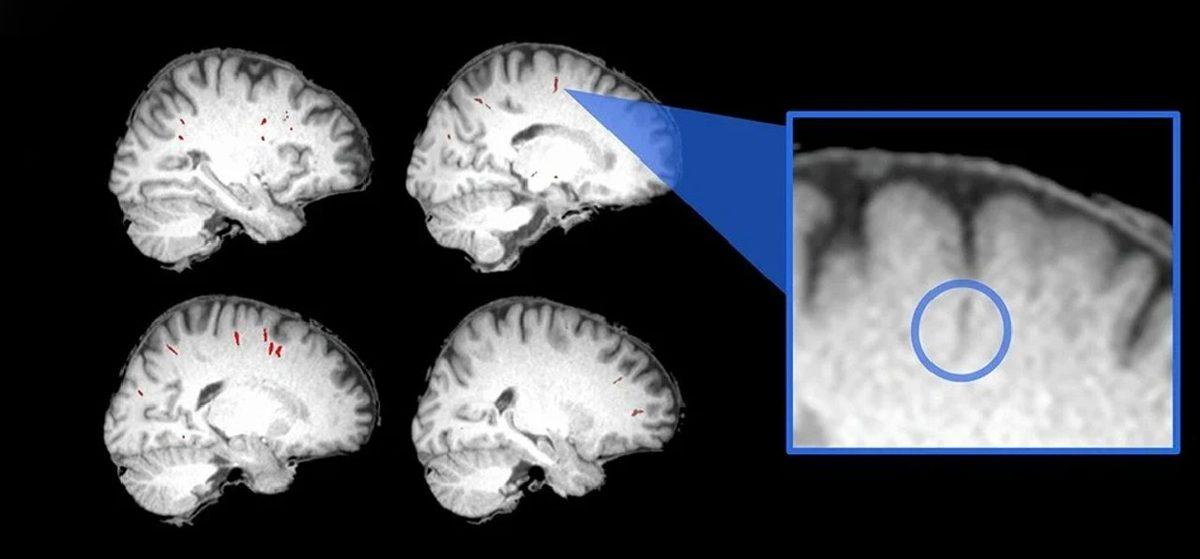

ABD'nin dört bir yanından araştırmacılar, 15 astronotun beyinlerinin, Uluslararası Uzay İstasyonuna gitmeden öncesine ve dönüşlerinden altı ay sonrasına ait bir dizi manyetik rezonans görüntüsü (MRI) taramasını karşılaştırdı. Sıvıların dengesini kolaylaştırdığı düşünülen beyin dokusundaki boşluklar olan perivasküler boşlukların boyutlarını dikkatlice değerlendirmek için algoritmalar kullanan ekip; yörüngede geçirilen zamanın, en azından ilk kez uzaya çıkanların beyin damar yolları üzerinde derin bir etkisi olduğunu tespit etti.

Beynimizden geçen kan damarlarını çevreleyen alanlara odaklanarak, mikro yerçekiminin biyolojimiz üzerindeki çarpıtma etkisine ilişkin yapılan en son değerlendirmelere göre astronotlar, görevler arasında endişe verici değişikliklere maruz kalıyor.